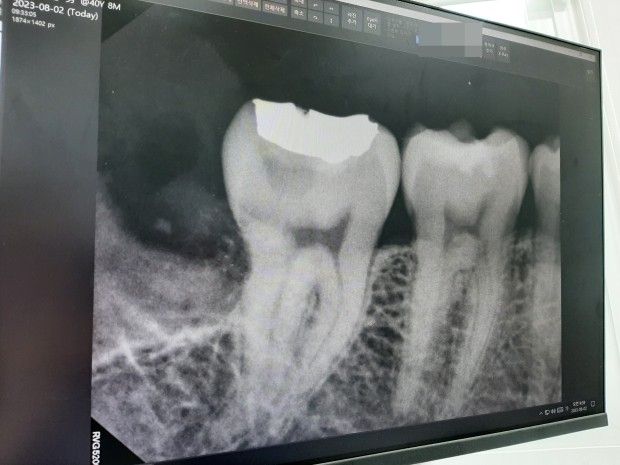

발치 후 사진입니다. (발치하면서 사랑니에 충치 의심 흔적이 있다고 설명해주셨고요.)

1. 충치가 잇몸 하방 뼈 있는 곳과 아주 근접해 있기 때문에 치료가 쉽지 않다는 의미입니다. 충치 경과는 6개월에 한번 정도 내원하셔서 체크하시면 됩니다. (충치일 수도 있고 치근이라고 하는 치아 뿌리가 사랑니에 의해 흡수된 것일 수도 있습니다.)

2. 혹시 두번째 큰 어금니(47번) 인레이 치료는 타 치과에서 받으셨나요? 동일한 치과에서 했다면 아마 기록이 남아 있을텐데 충치가 아닐 확률도 있습니다. 보통 인레이 하방에 생기는 충치를 이차충치라고 하는데 사진으로만 봐서는 충치라고 하기에는 다소 변연이 매끄럽습니다. 즉, 골드인레이 치료 당시 저기까지 충치가 있었어서 깊게 파내고 투과성 재료 또는 시간이 지남에 따라 분해되는 재료로 메워뒀을 수도 있습니다. 골드인레이가 깨지거나 부러진 곳이 없다면 충치가 아닐 확률이 높습니다. 이차 충치는 기본적으로 뭔가 틈새가 있어야 그 사이로 음식물과 침이 섞여 들어가면서 감염되어 충치가 생기는 것입니다. 특별히 찬것에 시리거나 단것 먹었을 때 아픈 증상이 있는지도 한번 확인해보시기 바랍니다.

사진에 보는부분은 충치일수도 잇지만 예전에 인레이를 치료할때 충치가 깊어서 보호하는 약재가 저렇게 보일수도 있습니다. 일단 증상이 없으면 지켜보시는게 좋을것같습니다.

사진으로 음영이 보이는 부위는 충치이거나 방사선 투과 성이 있는 재료로 충전을 했을수 있습니다.